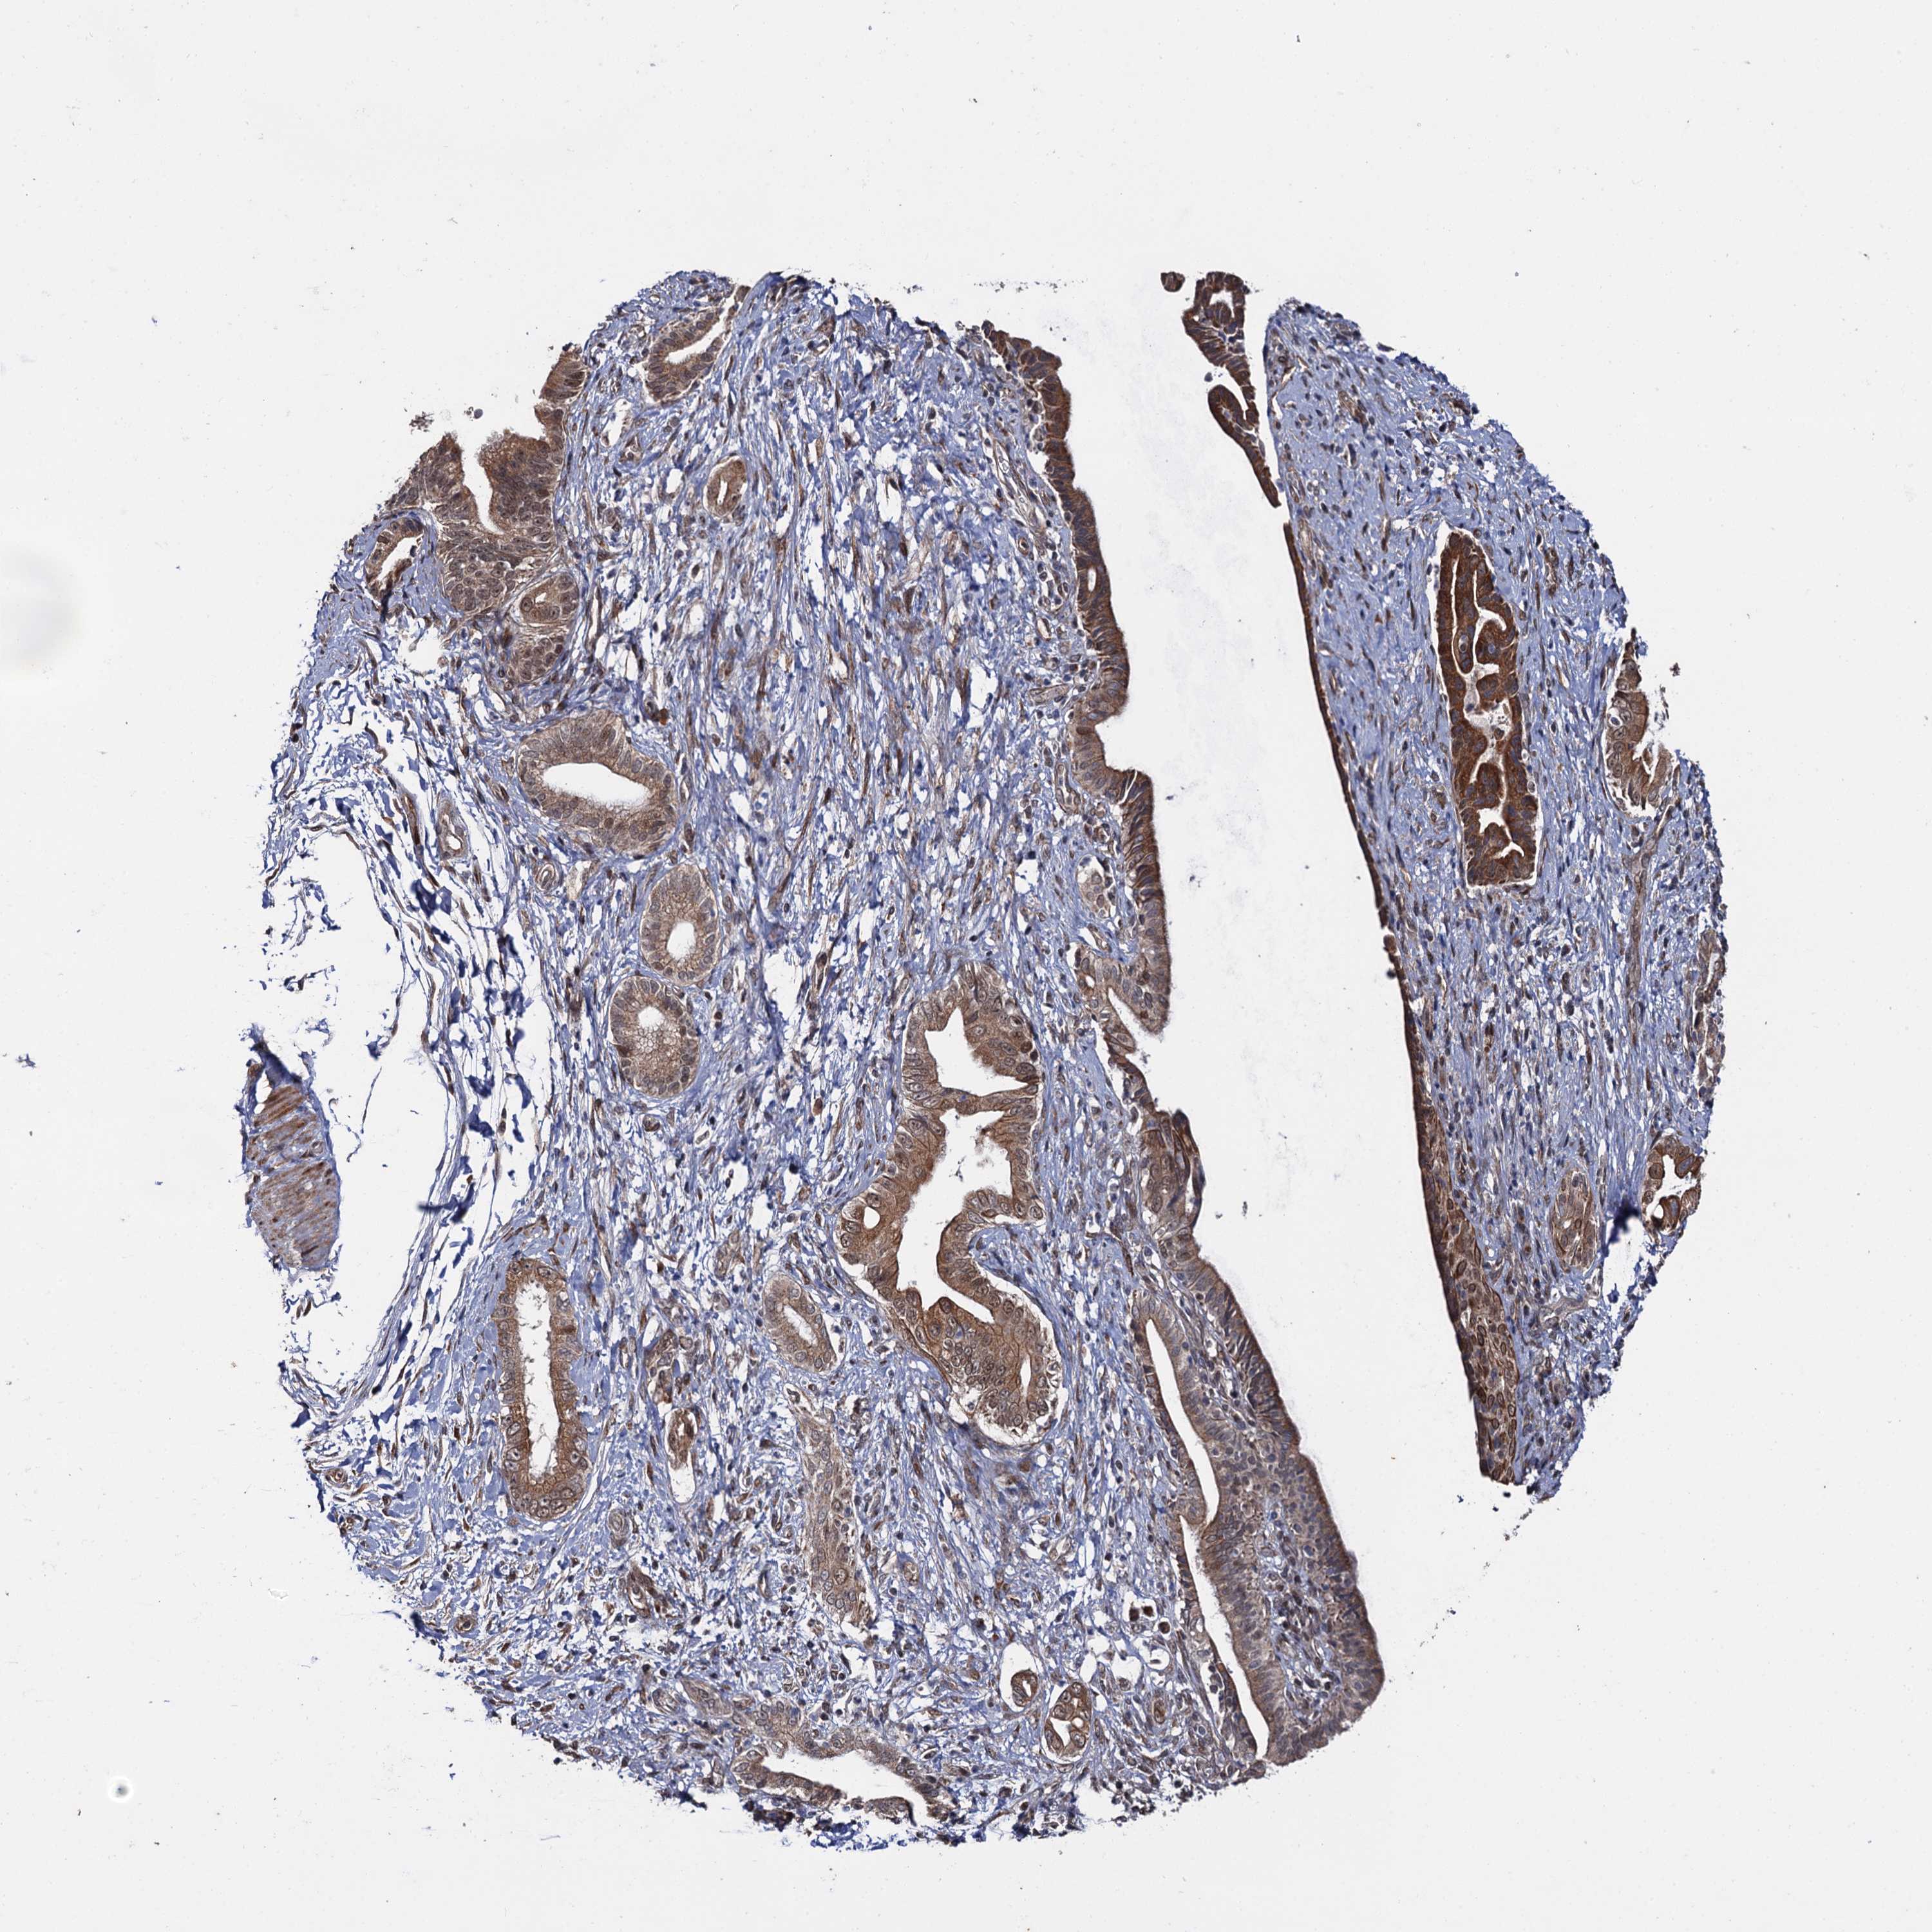

PANCREATIC CANCER - Protein expressioni

A mouse-over function shows sample information and annotation data. Click on an image to view it in a full screen mode. Samples can be filtered based on level of antibody staining by selecting one or several of the following categories: high, medium, low and not detected. The assay and annotation is described here.

Note that samples used for immunohistochemistry by the Human Protein Atlas do not correspond to samples in the TCGA dataset.

Antibody stainingi

Antibody staining in the annotated cell types in the current human tissue is reported as not detected, low, medium, or high, based on conventional immunohistochemistry profiling in selected tissues. This score is based on the combination of the staining intensity and fraction of stained cells.

Each image is clickable and will lead to virtual microscopy that enables deeper exploration of all samples and also displays staining intensity scores, fraction scores and subcellular localization as well as patient and tissue information for each sample.

Antibody HPA039318

Antibody HPA039763

Adenocarcinoma, NOS